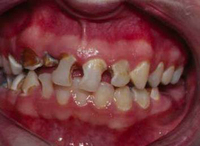

Poor oral hygiene with lack of dental care and resultant rampant decay

From the personal collection of Melanie S. Lang and Thomas B. Dodson